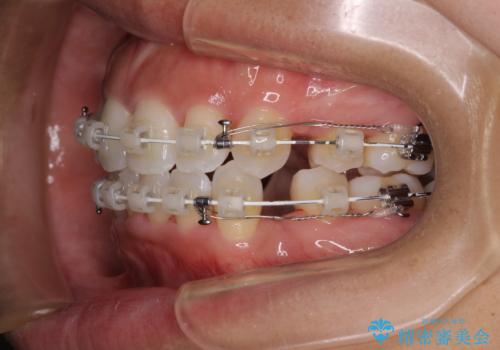

- 審美装置

上下顎ともに前突した歯列であったので、上下ともに左右の第1小臼歯4本を抜歯し、ワイヤー装置にて矯正治療を行うこととしました。

抜歯スペースに前歯を移動させることで歯の突出感が改善され、非常に唇が閉じやすい仕上がりとなりました。